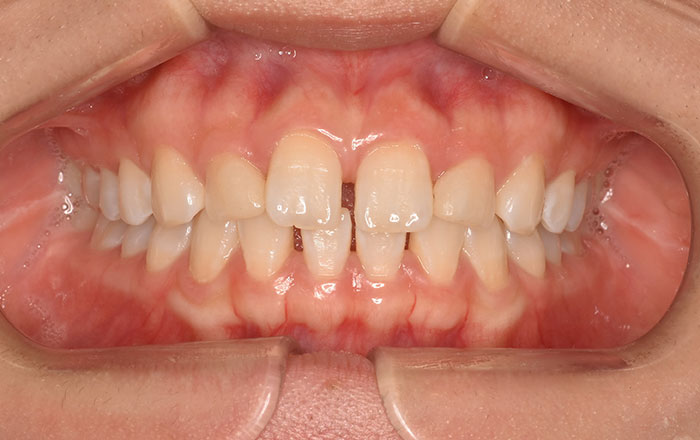

①頬の内側、舌の横に付く歯の痕

②上顎下顎にできる骨隆起

③ほっぺの内側に歯の跡がつく

このような症状があると歯ぎしり、食いしばりをしている可能性があります。